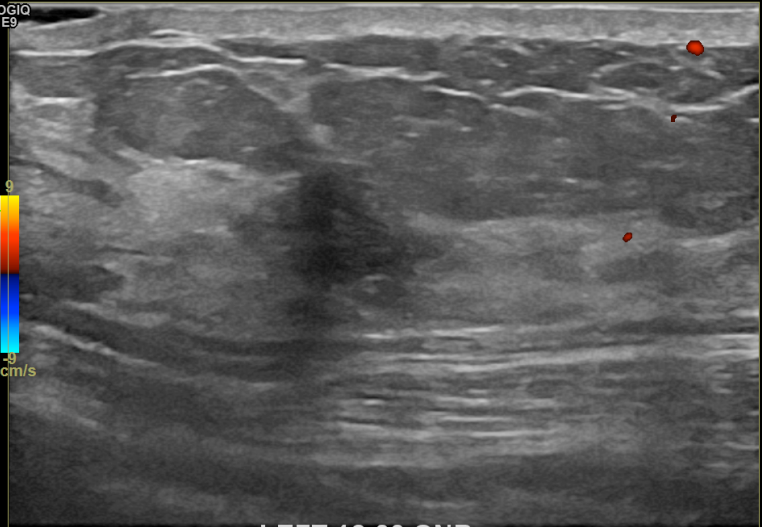

상기환자 외부검사이상으로  내원하신 40대 중반 여성분으로 의심스러운

좌측혹 조직검사 시행해 침윤성암으로 진단되었습니다